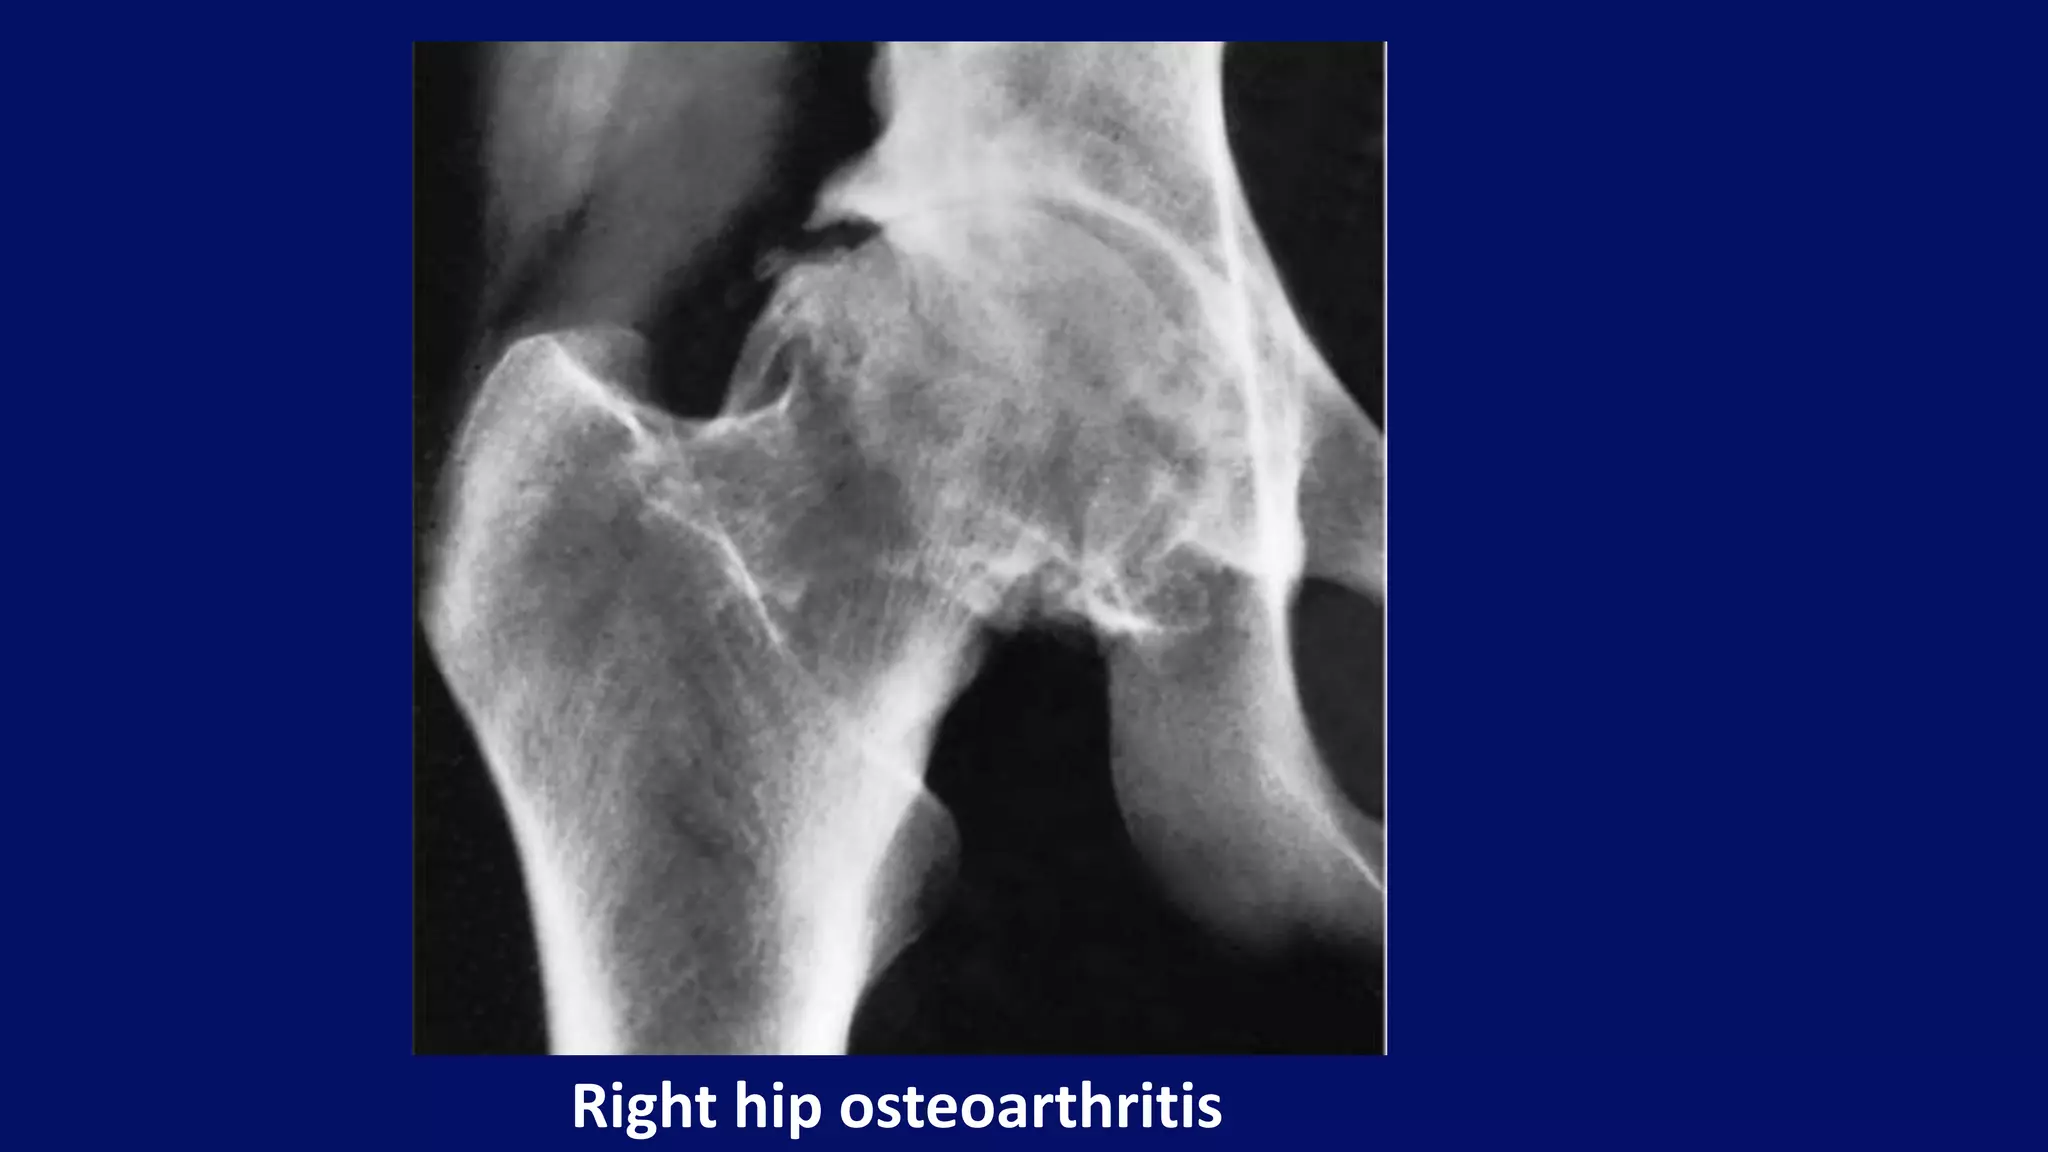

Right hip osteoarthritis

Superolateral migration of femoral head with typical Eggers cyst in acetabulum.

Osteoarthritis of Large joints

narrow joint space

subchondral sclerosis

osteophytes